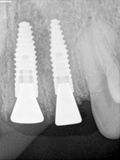

fredlibc | all galleries >> Galleries >> RYang - 11 + immediate 21 and 22 > R5.jpg

R5.jpg